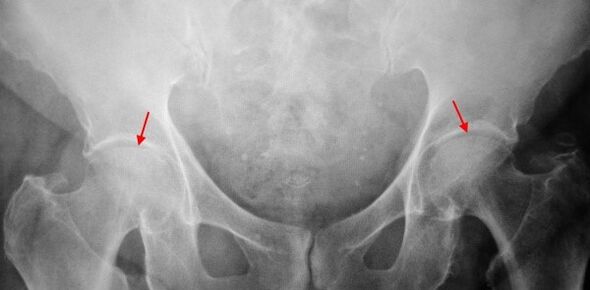

On X -Raj patient that suffers from coxartrosis 1. The degree is determined: moderately uneven narrution of a common gap, as well as the growth of bones around the outer or internal edge of acetabulum in the lack of changes from the head and the femur of the femur.

In X -Ray image for cooperation 2. degrees, significantly uneven narrowing of the common gap (more than half of the normal height).The federal head slung to the upward, deformed and increasing size, and its contours become uneven.The growth of bones with this degree of coxartrosis appear only on the inner, but also on the outer edge of acetabulum and go beyond the cartilage.

On the coxartrose radiograms 3. The degree revealed sharply of shared spaces, expressed the spread of the thigh head and multiple growth of bone bones.

The diagnosis of coxartrosis is based on clinical signs and additional studies data, of which the main radiography is.In many cases, the X -Rays allows you to establish not only the degree of coextress, but also the cause of its phenomenon.Thus, for example, the increase in the corners of the neck-diaphone varnish, scenes and flattening of acetabulum indicate displasia and changes in the form of the Čutna bone indicated that coxartrosis is the consequence of Perres' disease or youthful epiphysiolysis.On the radiographs of patients with the coxarter, the changes can be disclosed to indicate injuries.